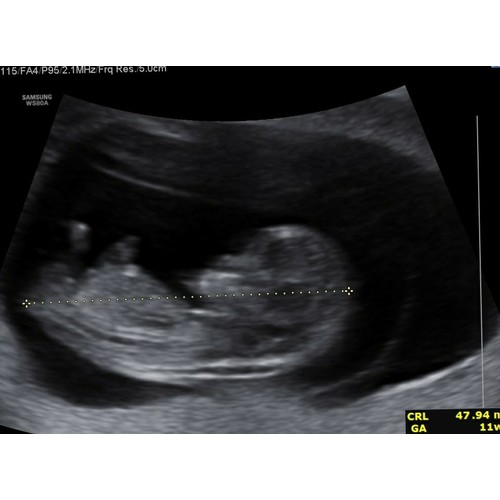

Dit was vrijdag met 10.6. Heel leuk om de armpjes en beentjes te zien bewegen. En echt uitgebreide echo gehad, hebben de doorsnede van de hersenen gezien (dan zie je een soort vlinder) en de maag en blaas (gewoon een zwarte stip 😂). Echt bizar wat er allemaal al in zo’n klein frummeltje zit!